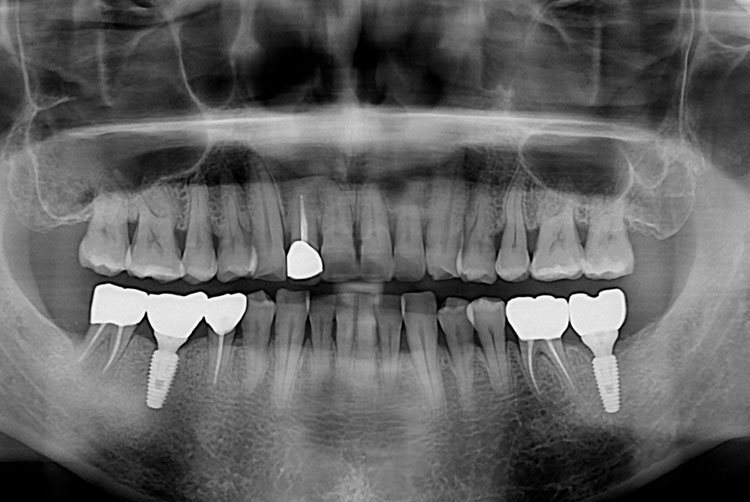

엄윤득_후.jpg

치료후 : 2017-10-04

세종치과는 많은 환자와 다양한 케이스를 바탕으로 항상 편안한 임플란트 수술을 제공하고자 노력하고,

오래동안 튼튼히 쓸 수 있는 임플란트 수술을 가장 큰 목표로 삼고 있습니다.